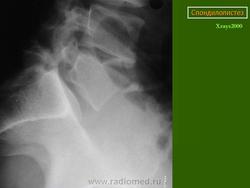

Рис.3a,b,c. Истмический спондилолистез (спондилолиз). a) Рентгенограмма поясничного отдела позвоночника. Стрелкой указана зона дефекта (спондилолиза) дужки L5 позвонка. b) Компьютерная томограмма (КТ) L5 позвонка. Стрелкой указана зона дефекта (спондилолиза) дужки L5 позвонка. с) Магнитно-резонансная томографи (МРТ) поясничного отдела позвоночника. Стрелкой указано смещение L5 позвонка кзади I степени.